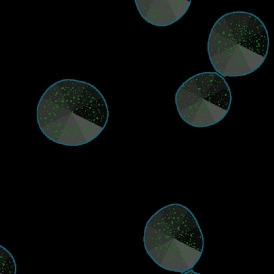

The IF Spheroids App allows a comprehensive analysis of spheroids (as well as organoids and embryoid bodies). It automatically identifies the spheroids and cells based on the nuclei staining and analyzes two additional IF markers. It segments the cells into different cellular compartments, including membrane, nuclei, and cytosol, and further measures the marker expression for each compartment. It can also measure dot markers (if available). It establishes proximity distances for the cells detected within the spheroids, bringing the IF-stained cell populations into spatial context.